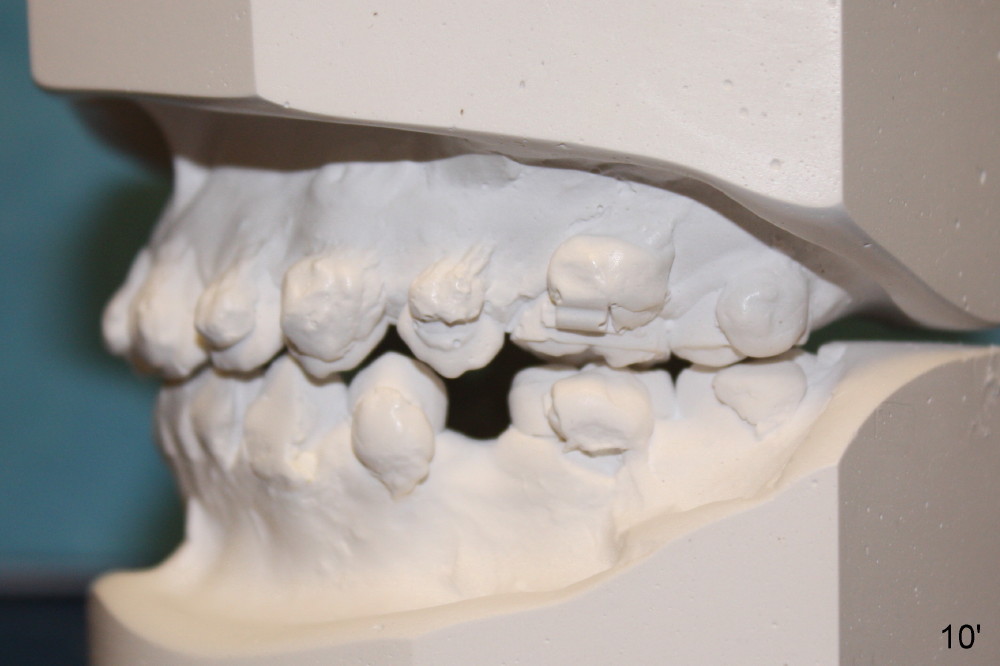

A 13-year-old Asian girl seeks orthodontic treatment for crowding. The lower 2nd bicuspids are congenitally missing (Fig.1,8), whereas the upper right one rotates 180° and the upper left is partially impacted (Fig. 1, 7). The lip muscles strain when the lips close (Fig.3). Orthodontic treatment started with extraction of four affected teeth (#4,13, K and T) 6 months ago. .018' niti wires are being used. Dental midlines do not coincide preop and intraop (Fig.4,4'). Pre-op front view shows that the upper dental midline coincides with the facial one (Fig.1'). There is Class I canine and molar relationship on the right (Fig.5,5',9,9'); open bite on the left (Fig.6,6',10,10').

Update: The left open bite was closed less than one month by wearing elastics between upper and lower teeth (Fig. 6'''). The occlusal plane and midline improve (Fig.4''). Wires have gradually changed to .016x.016, .016x.022 and now .018x.025 with power chains. All the spaces are closed except the one in LR (Fig.7''-10''). What I cannot accomplish is to fix meisal (Fig.5'' (white line), 9'') and lingual (Fig.8'' arrows) inclination of LR molars, although elastic is instructed to be placed between UR7 buccal and LR7 lingual. The rectangular wires could be twisted to fix lingual inclination. Which should be done first: LR space or LR molar inclination? Click each figure for magnification.